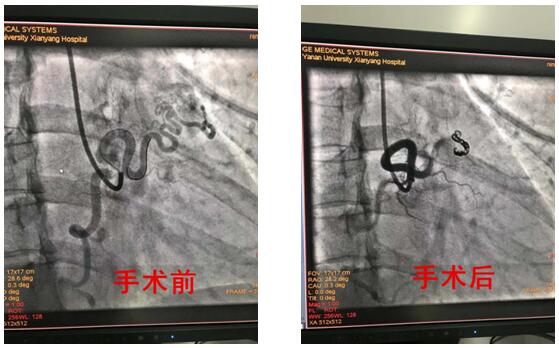

2019年8月15日對(duì)于延安大學(xué)咸陽醫(yī)院心血管病院心內(nèi)VIP病區(qū)是一個(gè)不尋常的日子,因?yàn)檫@一天王明新主任及王顯利主任介入團(tuán)隊(duì)完成了又一例右冠狀動(dòng)脈---左心房瘺封堵術(shù)。

患者為39歲青年女性,反復(fù)發(fā)生心絞痛,冠脈造影示:右冠-左心房瘺道血管粗大,與右冠脈直徑相當(dāng)。結(jié)合患者癥狀,考慮右冠嚴(yán)重竊血引發(fā)胸痛癥狀。心內(nèi)VIP介入團(tuán)隊(duì)在仔細(xì)詢問病史、認(rèn)真查體及詳細(xì)的術(shù)前評(píng)估后于8月15日在導(dǎo)管室行彈簧圈封堵術(shù),手術(shù)歷經(jīng)2小時(shí),術(shù)程順利,術(shù)后患者未訴不適,安返病房,術(shù)后嚴(yán)密監(jiān)測(cè)血壓、心率等生命體征均平穩(wěn)。

冠狀動(dòng)脈瘺指冠狀動(dòng)脈與心臟或大血管存在先天性異常交通,多為先天畸形,以右冠狀動(dòng)脈瘺多見,占50%-60%,引入右心系統(tǒng)最為常見,占90%左右,以右冠狀動(dòng)脈--右室瘺常見,而通入左房左室相對(duì)罕見,心內(nèi)VIP病區(qū)完成的這例手術(shù)恰恰是右冠狀動(dòng)脈--左房瘺。